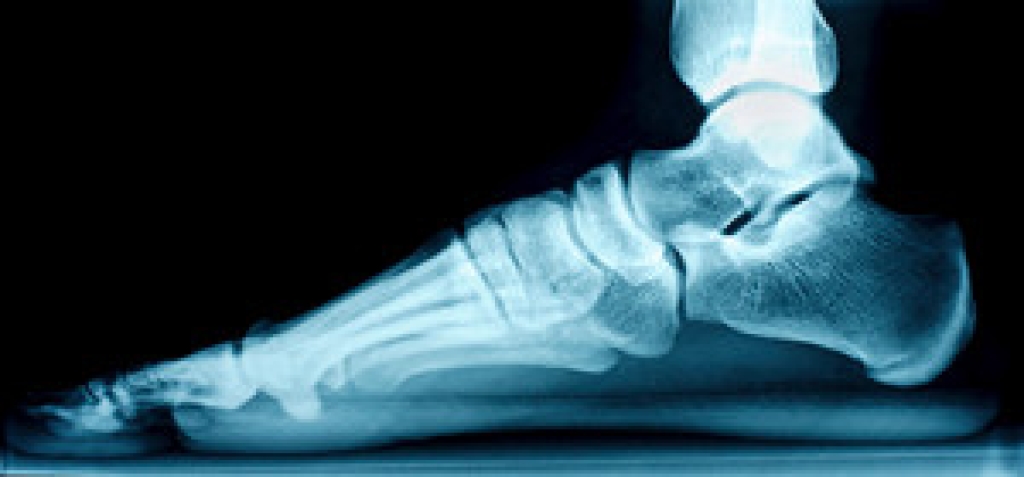

A calcium build-up on the underside of the heel may indicate a heel spur has developed. It can happen by increasing speed and distance too quickly while running or by wearing shoes with inadequate support. Additionally, medical conditions such as rheumatoid arthritis may cause a heel spur to develop. Regardless of the cause, a heel spur can be painful, and walking can become difficult. A diagnosis is often performed, which consists of having an X-ray taken. This is successful in ruling out a fractured heel bone. The symptoms associated with a heel spur can include sharp pain under the foot, which may become worse after a prolonged time of rest, and the affected foot may feel warm when touched. Treatment can begin with elevating the foot and temporarily stopping the activity that may have caused the heel spur. Performing specific stretches may help to alleviate some of the discomfort, as well as to maintain a healthy weight. If you have heel pain, it is strongly suggested that you speak to a podiatrist as soon as possible who can effectively diagnose and treat heel spurs.

Heel spurs are formed by calcium deposits on the back of the foot where the heel is. This can also be caused by small fragments of bone breaking off one section of the foot, attaching onto the back of the foot. Heel spurs can also be bone growth on the back of the foot and may grow in the direction of the arch of the foot.